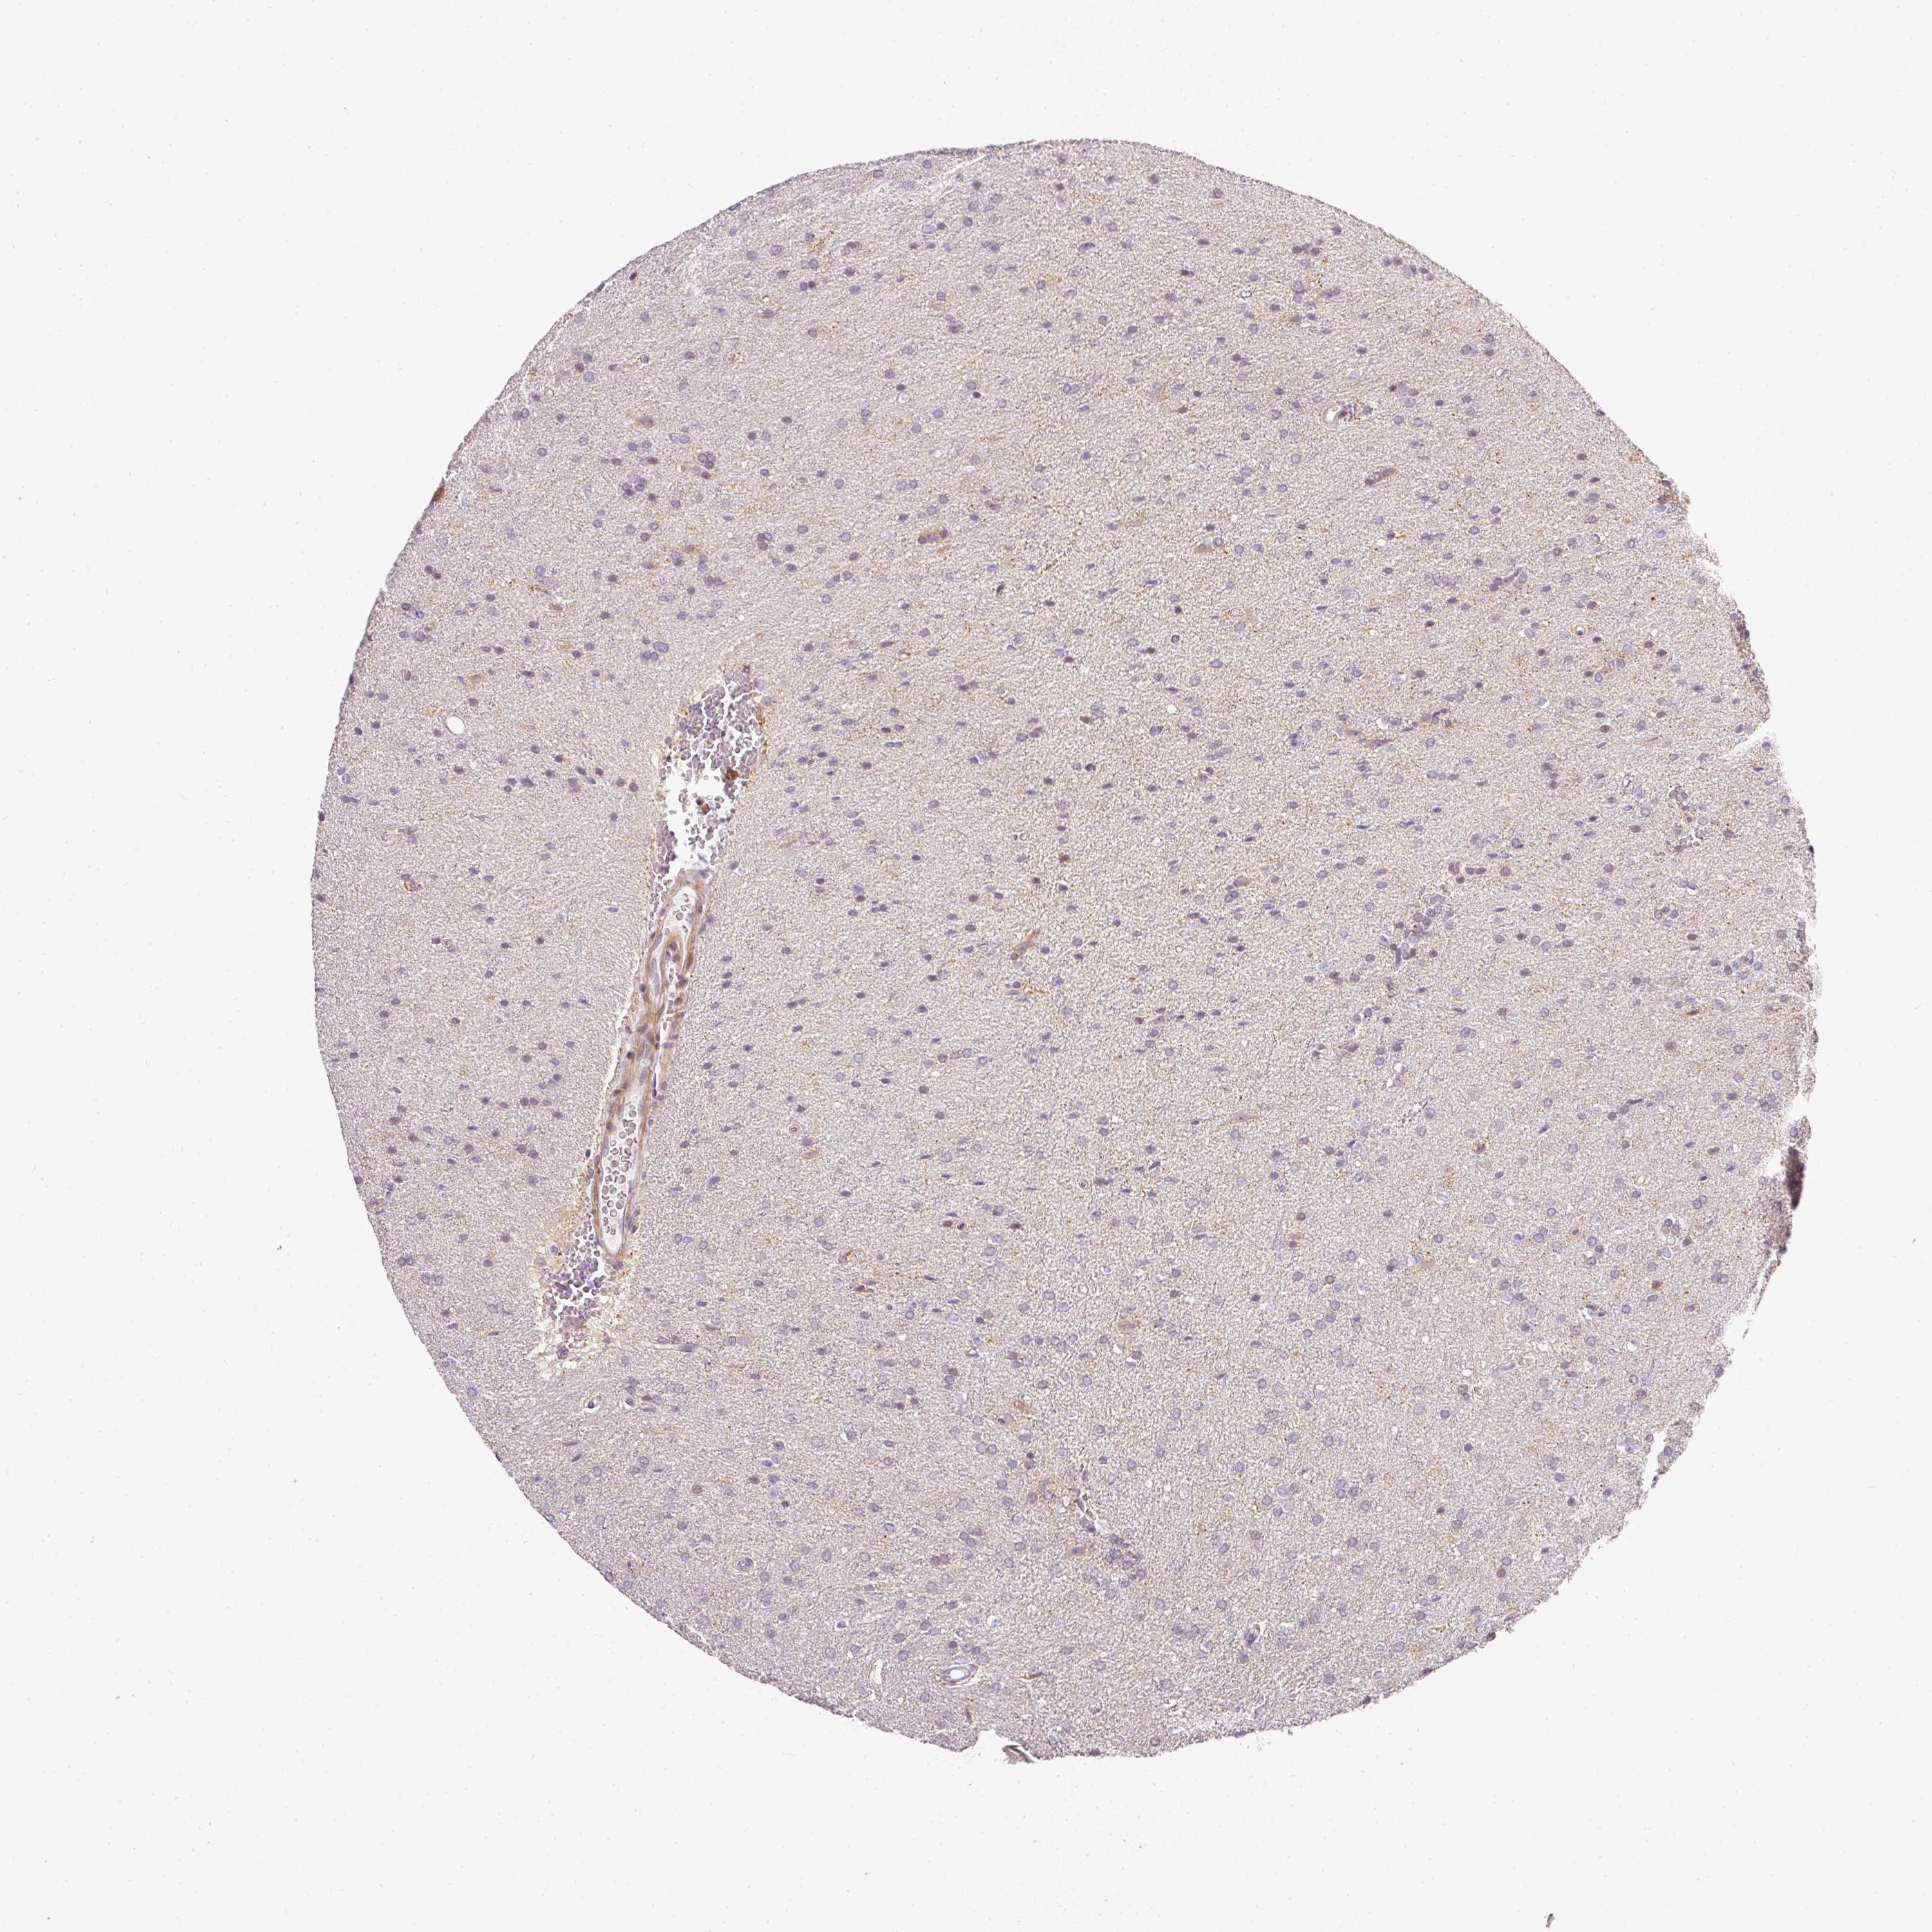

GLIOMA - Protein expressioni

A mouse-over function shows sample information and annotation data. Click on an image to view it in a full screen mode. Samples can be filtered based on level of antibody staining by selecting one or several of the following categories: high, medium, low and not detected. The assay and annotation is described here.

Note that samples used for immunohistochemistry by the Human Protein Atlas do not correspond to samples in the TCGA dataset.

Antibody stainingi

Antibody staining in the annotated cell types in the current human tissue is reported as not detected, low, medium, or high, based on conventional immunohistochemistry profiling in selected tissues. This score is based on the combination of the staining intensity and fraction of stained cells.

Each image is clickable and will lead to virtual microscopy that enables deeper exploration of all samples and also displays staining intensity scores, fraction scores and subcellular localization as well as patient and tissue information for each sample.

Antibody HPA047050

Antibody HPA050583

Glioma, malignant, High grade

Glioma, malignant, Low grade

Glioblastoma, NOS